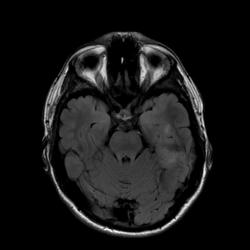

Коллеги! Пожалуйста, помогите разобраться. Пациент 15 лет. Внезапно на фоне полного благополучия - единичный эпилептоподобный припадок. Травмы в последние несколько лет отрицает, однако со слов, была ЧМТ в раннем детстве. Занимается спортом и "вроде бы" когда-то были мелкие спортивные травмы (падения).

Я считаю, что это очаг ушиба головного мозга, однако под анамнез это не совсем подходит. Пожалуйста, ваши мнения.

утолщение коры левой    гиппокампальной области , деформация  борозд , повышение МРС по Т2 и FLAIR  , может это мальформацию кортикального развития- фокальная кортикальная  дисплазия -изменение коркового серого вещества с нарушением архитектоники коры.

Спасибо, Irena!

Остановились на этом варианте.